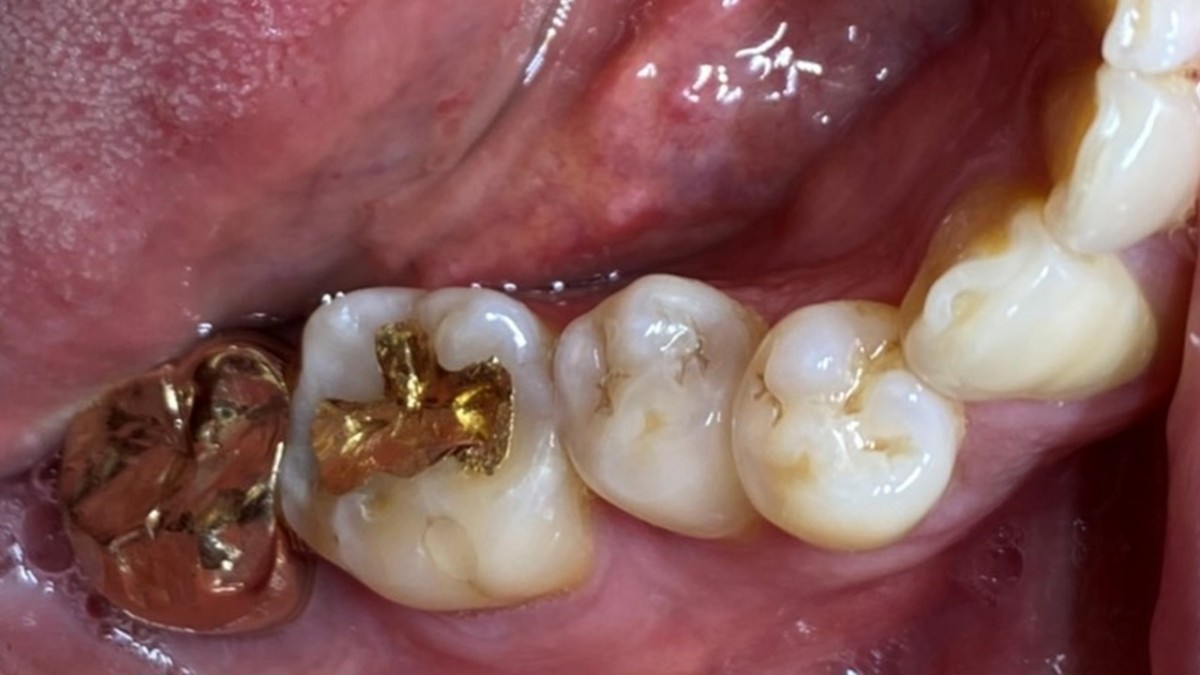

A 47-year-old male patient had a crown with an ill-fitting margin and crack-tooth syndrome in the lower 2nd molar. No systemic issue.